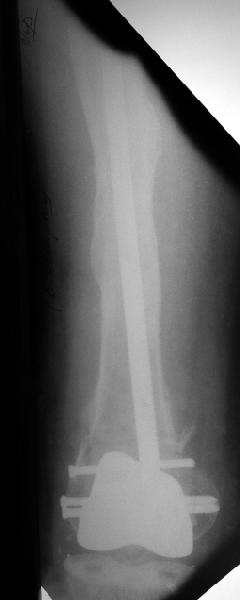

В итоге сделали антеградный остеосинтез. В дистракторе свежий перелом вправился сразу, а вот старый - оставил проблему, дистальный отлмомк остался все равно кзади. И гвоздь бы прошел кпереди от него, а ретроградный - перфорировал бы передний кортекс. Так что пришлось еще сделать чрескожную остеотомию через перелом, чтобы малость мобилизовать дистальный отломок. Снимки в прилжении.

Критика, комментарии, мнения?

The radiographs look excellent and a good outcome would be anticipated. The idea to osteotomize the femur shaft to compensate for the prior shaft malunion was clever and should work fine.

I can't actually see the osteotomy on either radiograph. Is it more proximal than we see in these radiographs or so well aligned as to be not visible?